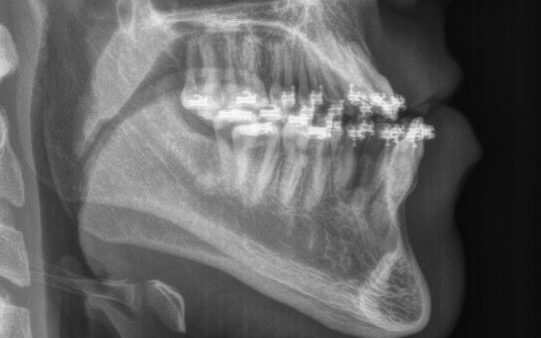

Jaw Surgery